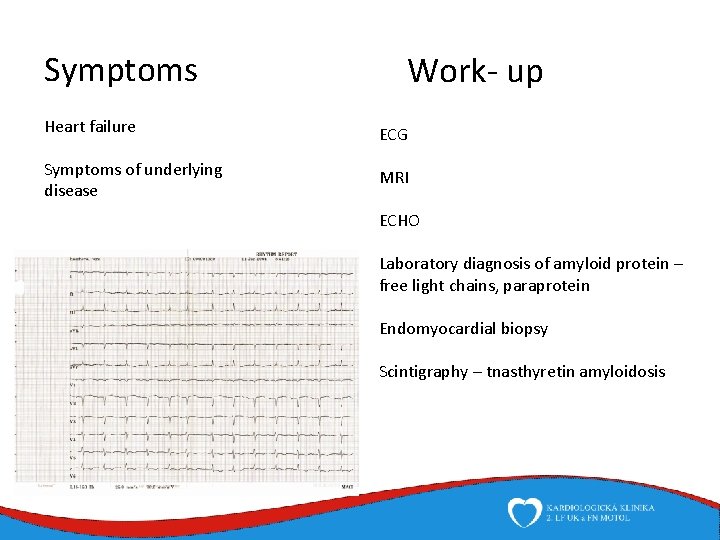

Symptoms Work- up Heart failure ECG Symptoms of underlying disease MRI ECHO Laboratory diagnosis of amyloid protein – free light chains, paraprotein Endomyocardial biopsy Scintigraphy – tnasthyretin amyloidosis